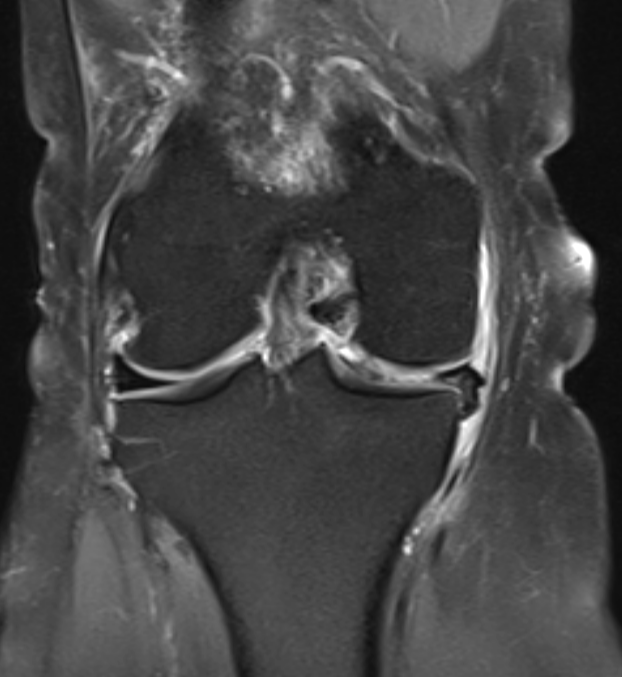

3. Bucket handle tear of medial meniscus